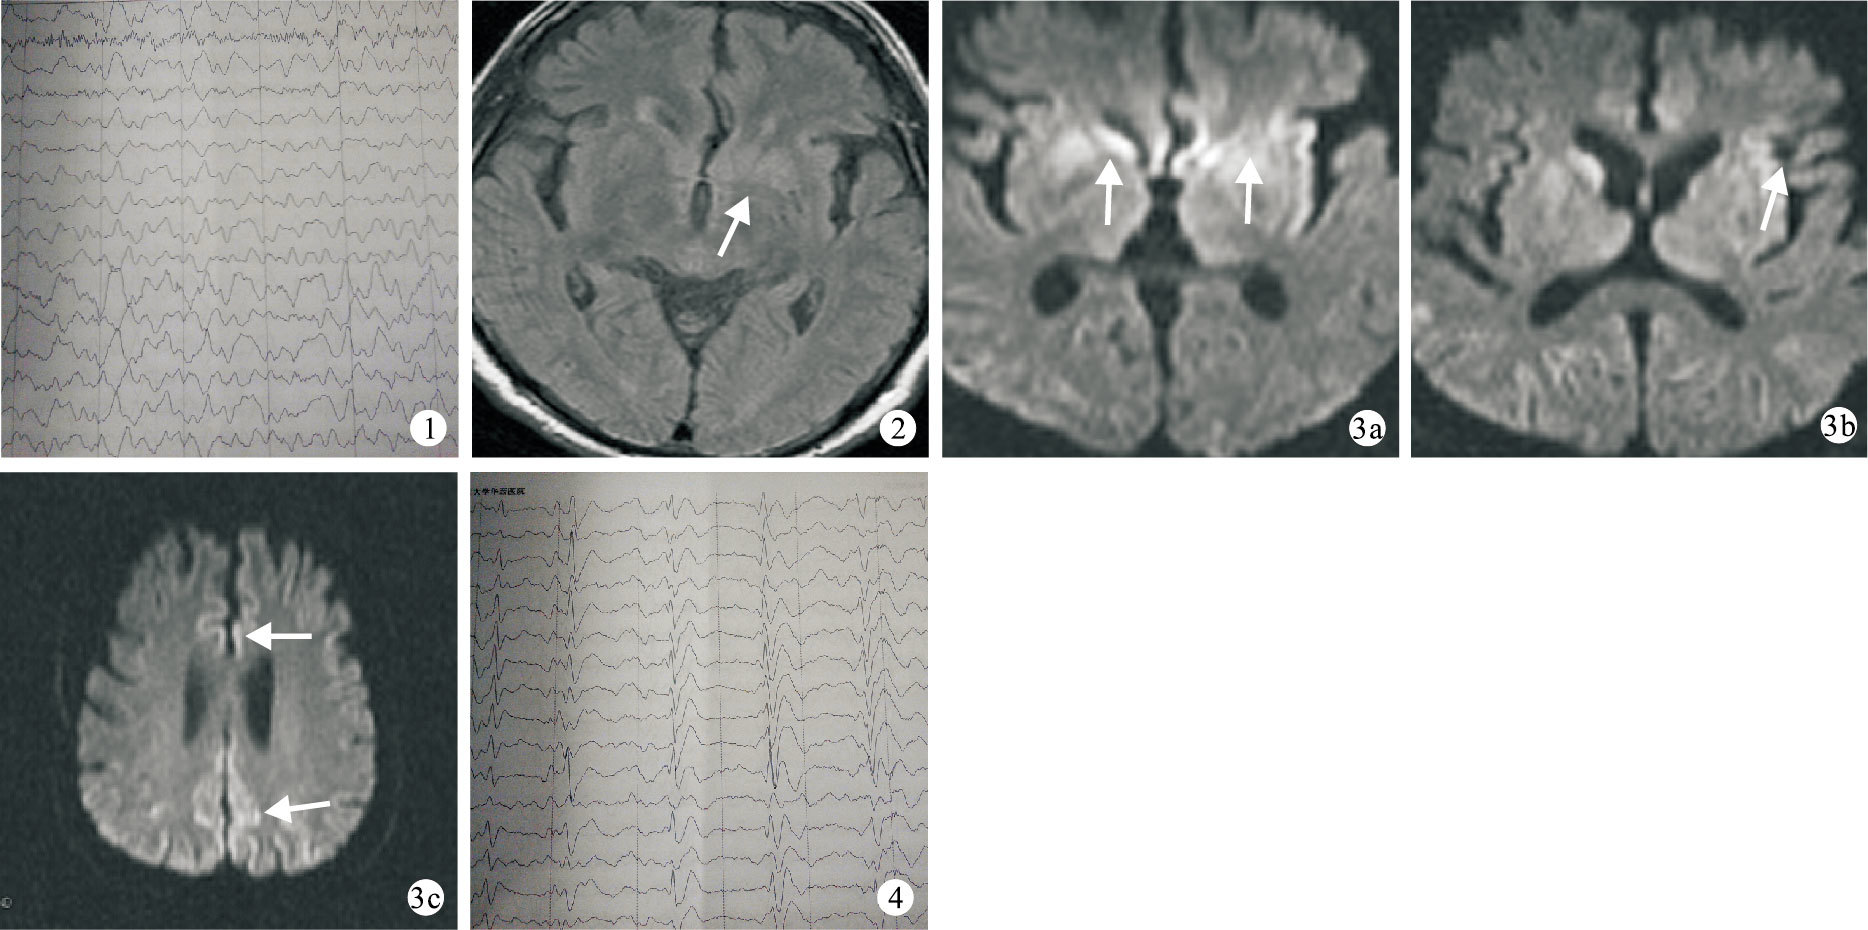

腦電圖雙側彌漫性慢波,病程2+個月 ? ?圖 2 頭部FLAIR像左側基底節區高信號影(白箭),病程1+個月 ? ? 圖 3頭部DWI像雙側基底節區(3a)、額顳頂枕島葉皮層(3b、3c)多發高信號影(白箭),病程2+個月 ? ? 圖 4腦電圖周期性三相波,病程4+個月

患者?男,67歲。因“記憶力下降伴行為異常2+個月”于2013年8月29日入院。2+個月前患者無明顯原因出現進行性近記憶力下降、伴性格改變,情緒不穩,易怒、易哭泣,并出現幻視、幻嗅、被害妄想,言語減少,語速減慢,動作遲緩。外院按“癡呆、病毒性腦炎”等治療,無明顯療效,患者癥狀仍呈進行性加重。1+個月前患者出現不認識家人,興奮、易激惹,伴言語不清、行走不穩、陣發性肢體抖動。家族史無特殊,否認嗜煙酒史。入院后體格檢查:體溫正常,生命體征穩定;譫妄狀態,對答不切題,構音障礙;四肢肌張力增高,雙上肢呈鉛管樣,四肢肌力5級,雙上肢可見摸索動作,強握反射陽性,四肢腱反射稍活躍,病理征陰性,醉漢步態、行走時需攙扶,可見肌陣攣。入院后查血常規、大小便常規、肝功能、腎功能、血糖、血脂、維生素B12濃度、腫瘤標志物(癌胚抗原、甲胎蛋白、非小細胞肺癌抗原、前列腺特異性抗原)、甲狀腺功能及相關抗體均在正常范圍;免疫全套(包括類風濕因子、抗可溶性抗原抗體譜)均陰性;銅藍蛋白320.0 mg/L;輸血前檢查乙型肝炎(乙肝)表面抗原半定量>3 000.000 COI、乙肝e抗體半定量>0.007 COI、乙肝核心抗體半定量>0.004 COI,艾滋病抗體(HIV)、梅毒抗體(TP)、丙型肝炎抗體(HCV)均陰性;烯醇化酶28.83 ng/mL;巨細胞病毒抗體IgG 2.80 U/mL,風疹病毒抗體Ig G16.50 U/mL,單皰病毒抗體Ⅰ/Ⅱ型IgG 19.30 Index。骨髓活體組織檢查(活檢)提示:骨髓造血細胞增生偏低下,三系均低,未見其他特殊病變;骨髓涂片提示:骨髓增生活躍,中性粒細胞63%,紅細胞24.5%。流式細胞術分析未見異常表型細胞群。9月2日腰椎穿刺壓力正常,腦脊液有核細胞2×106/L,蛋白0.46 g/L,涂片、培養未見異常;9月23日復查腰椎穿刺壓力正常,腦脊液細胞數0×106/L,蛋白0.46 g/L,涂片、培養均未見異常。腦電圖示:雙側彌漫性慢波,重度異常腦電圖(圖 1)。外院頭部MRI示:T1/T2加權像未見明顯異常,磁共振液體衰減反轉恢復序列(FLAIR)可見左側基底節區高信號影(圖 2)。入院后彌散加權成像(DWI)見雙側皮層、基底節區多發異常高信號影(圖 3)。患者家屬拒絕腦組織活檢及腦脊液14-3-3蛋白檢查,經全科討論并與家屬充分溝通后按可治療性疾病予阿昔洛韋、丙種球蛋白沖擊等診斷性治療,患者病情仍進行性加重。1+個月后患者意識狀態由譫妄轉為昏睡,并出現大小便失禁、發作性四肢抽搐。復查腦電圖提示典型周期性三相波(圖 4)。結合病史、頭部MRI及腦電圖典型表現,患者臨床診斷為散發型皮質-紋狀體-脊髓變性(CJD)。

本例患者在病程1+個月時FLAIR即提示基底節區(尾狀核、紋狀體)高信號,入院后(病程2+個月)DWI即提示雙側基底節區及皮層散在異常高信號影,而此時腦電圖的僅出現彌漫性慢波,直至患者病情進一步加重,在病程4+個月時,腦電圖才出現典型周期性三相波改變。可見,FLAIR及DWI異常遠遠早于腦電圖改變。